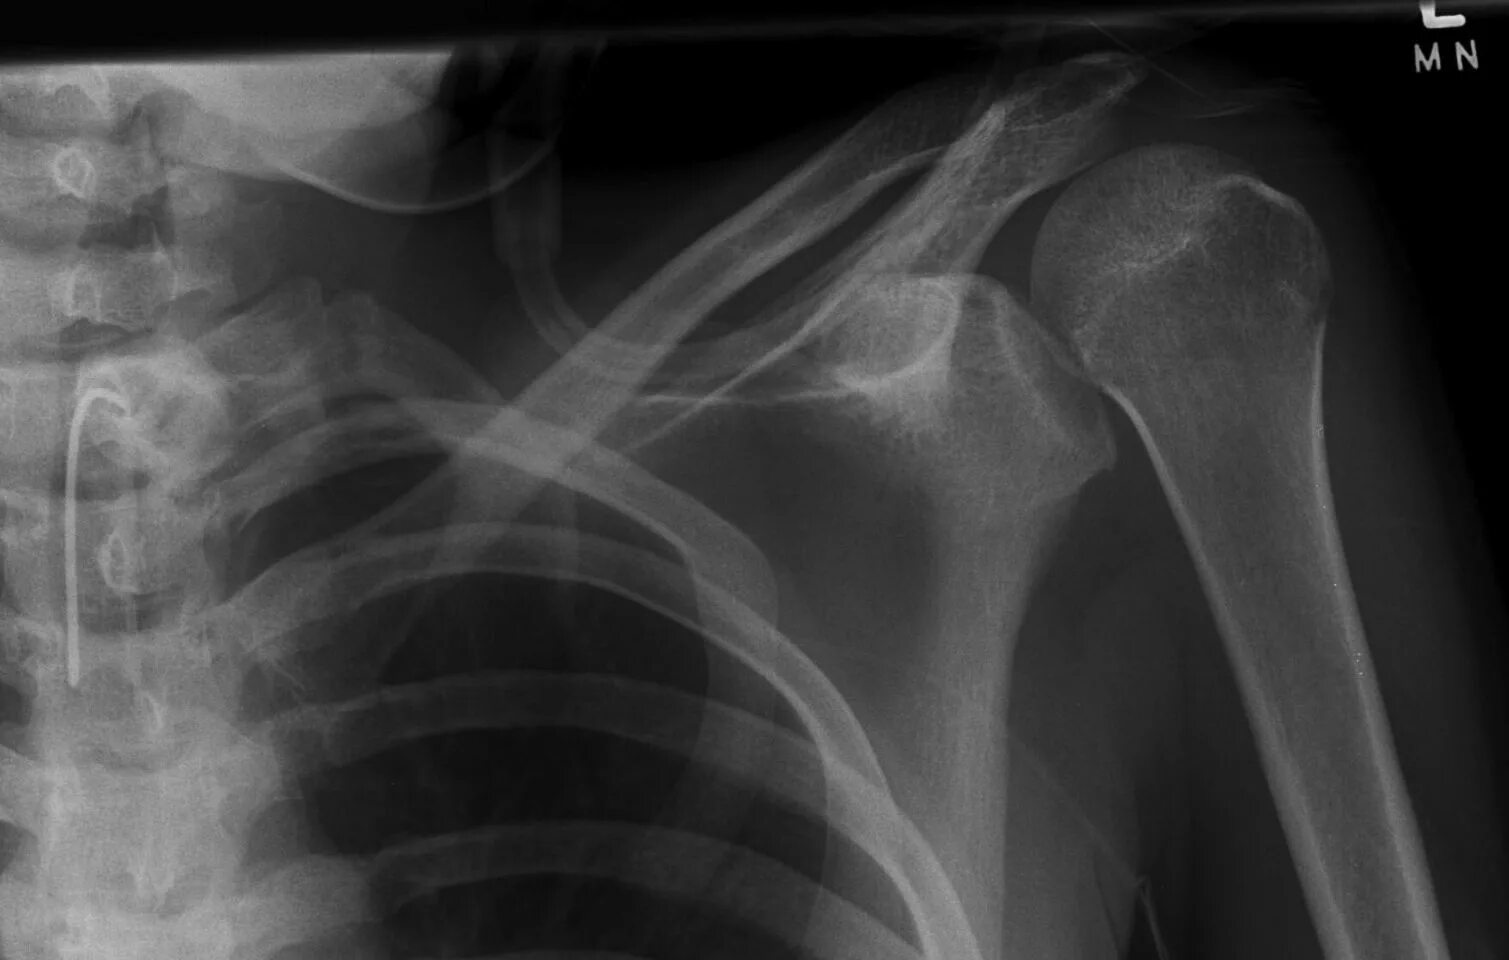

Вывих плеча вверх